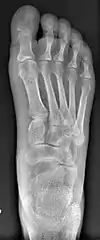

For recurrence correction after fusion procedure (Fig. 9) Metatarsus primus varus deformity and pain recurred 6 months after modified Lapidus procedure and it could also be again corrected by the syndesmosis procedure.